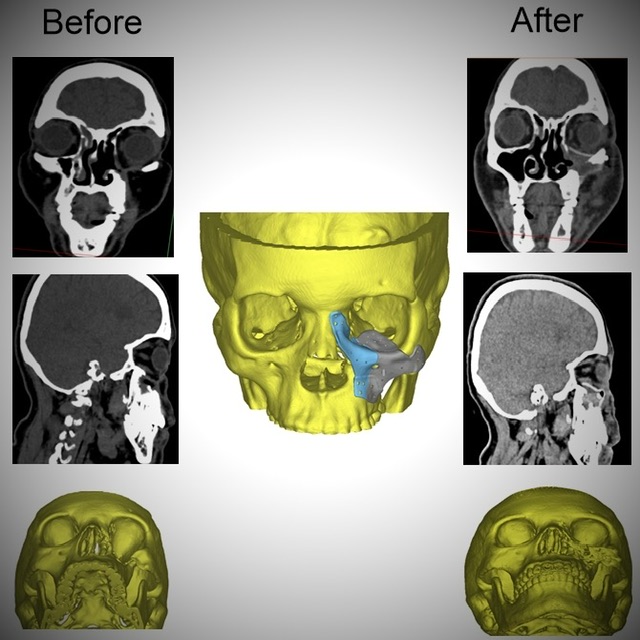

أطباء مستشفى الكرنك الدولي بالأقصر ينجحون في إعادة بناء عظام وجه سيدة بعد إصابتها بالفطر الأسود

استطاع أطباء جراحة الوجه والفكين وأورام الرقبة بمستشفى الكرنك الدولي بالأقصر من إعادة بناء عظام الوجه لسيدة أربعينية بعد تآكل عدة أجزاء منها نتيجة الإصابة بالفطر الأسود جراء جائحة كورونا.

وقال بيان لهيئة الرعاية الصحية، إن السيدة جاءت للمستشفى وهي تعاني من تسوس وتآكل بعظام الوجه وحجاج العين مما استدعى مثول السيدة للعديد من الجراحات التي أدت في النهاية لتشوه عظام الوجه على مدار 4 سنوات من المعاناة، وفقدت السيدة الأمل في مواجهة تحديات كبيرة نتيجة تشوه الوجه ورفض الكثير التدخل الجراحي.

وأضاف البيان، أن قسم جراحة الوجه والفكين بمستشفى الكرنك الدولي اتخذ القرار الطبي بعد استقرار حالة المريضة والمتابعة المستمرة للتأكد من إمكانية التدخل باستخدام التقنيات الحديثة لإعادة البسمة والأمل والثقة للسيدة في علاج التشوه الشديد بالوجه.

جراحة استغرقت 6 ساعات

وأشار البيان إلى استخدم القسم تصميم معقد مصنوع من مادة الـpeek والمستخدمة حديثًا في استيعاض عظام الوجه وذلك من خلال جراحة دقيقة استغرقت حوالي 6 ساعات.